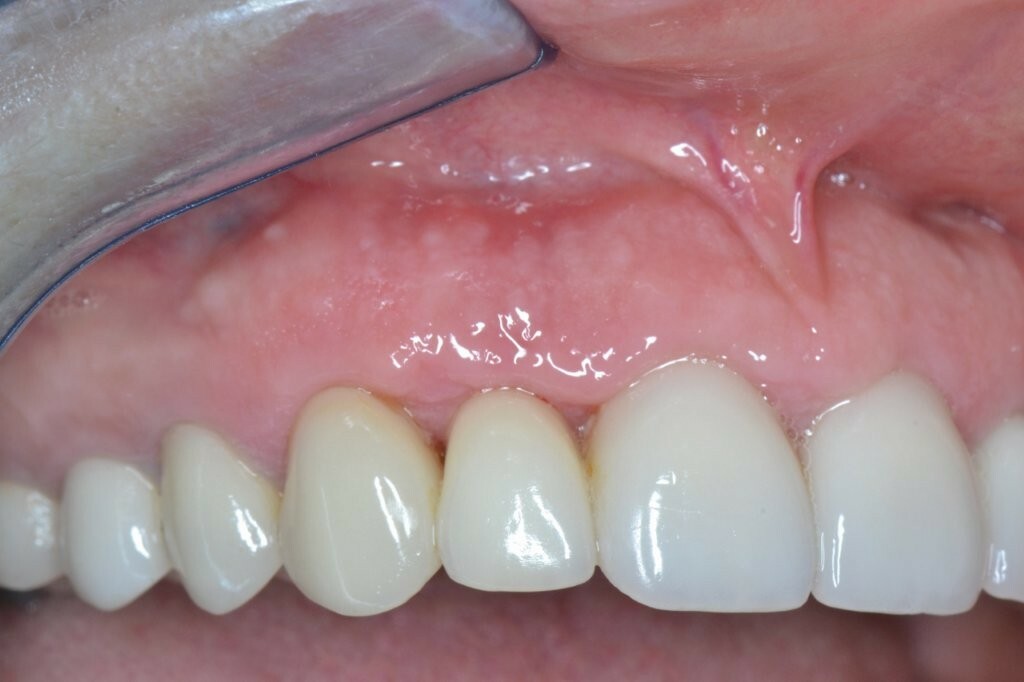

Sieben Wochen später wurde bei dem Patienten eine Kontrolluntersuchung durchgeführt. Zwar heilte die Wunde komplikationslos, die mesialen und distalen Papillen fehlten jedoch noch immer.

Dem Patienten wurde geraten, die OXYSAFE-Mundspülung einen weiteren Monat lang zu verwenden. Eine weitere Nachuntersuchung nach sechs Monaten zeigte eine ausgezeichnete Heilung des Weich- und Hartgewebes sowie eine schöne Regeneration der angrenzenden Papillen.